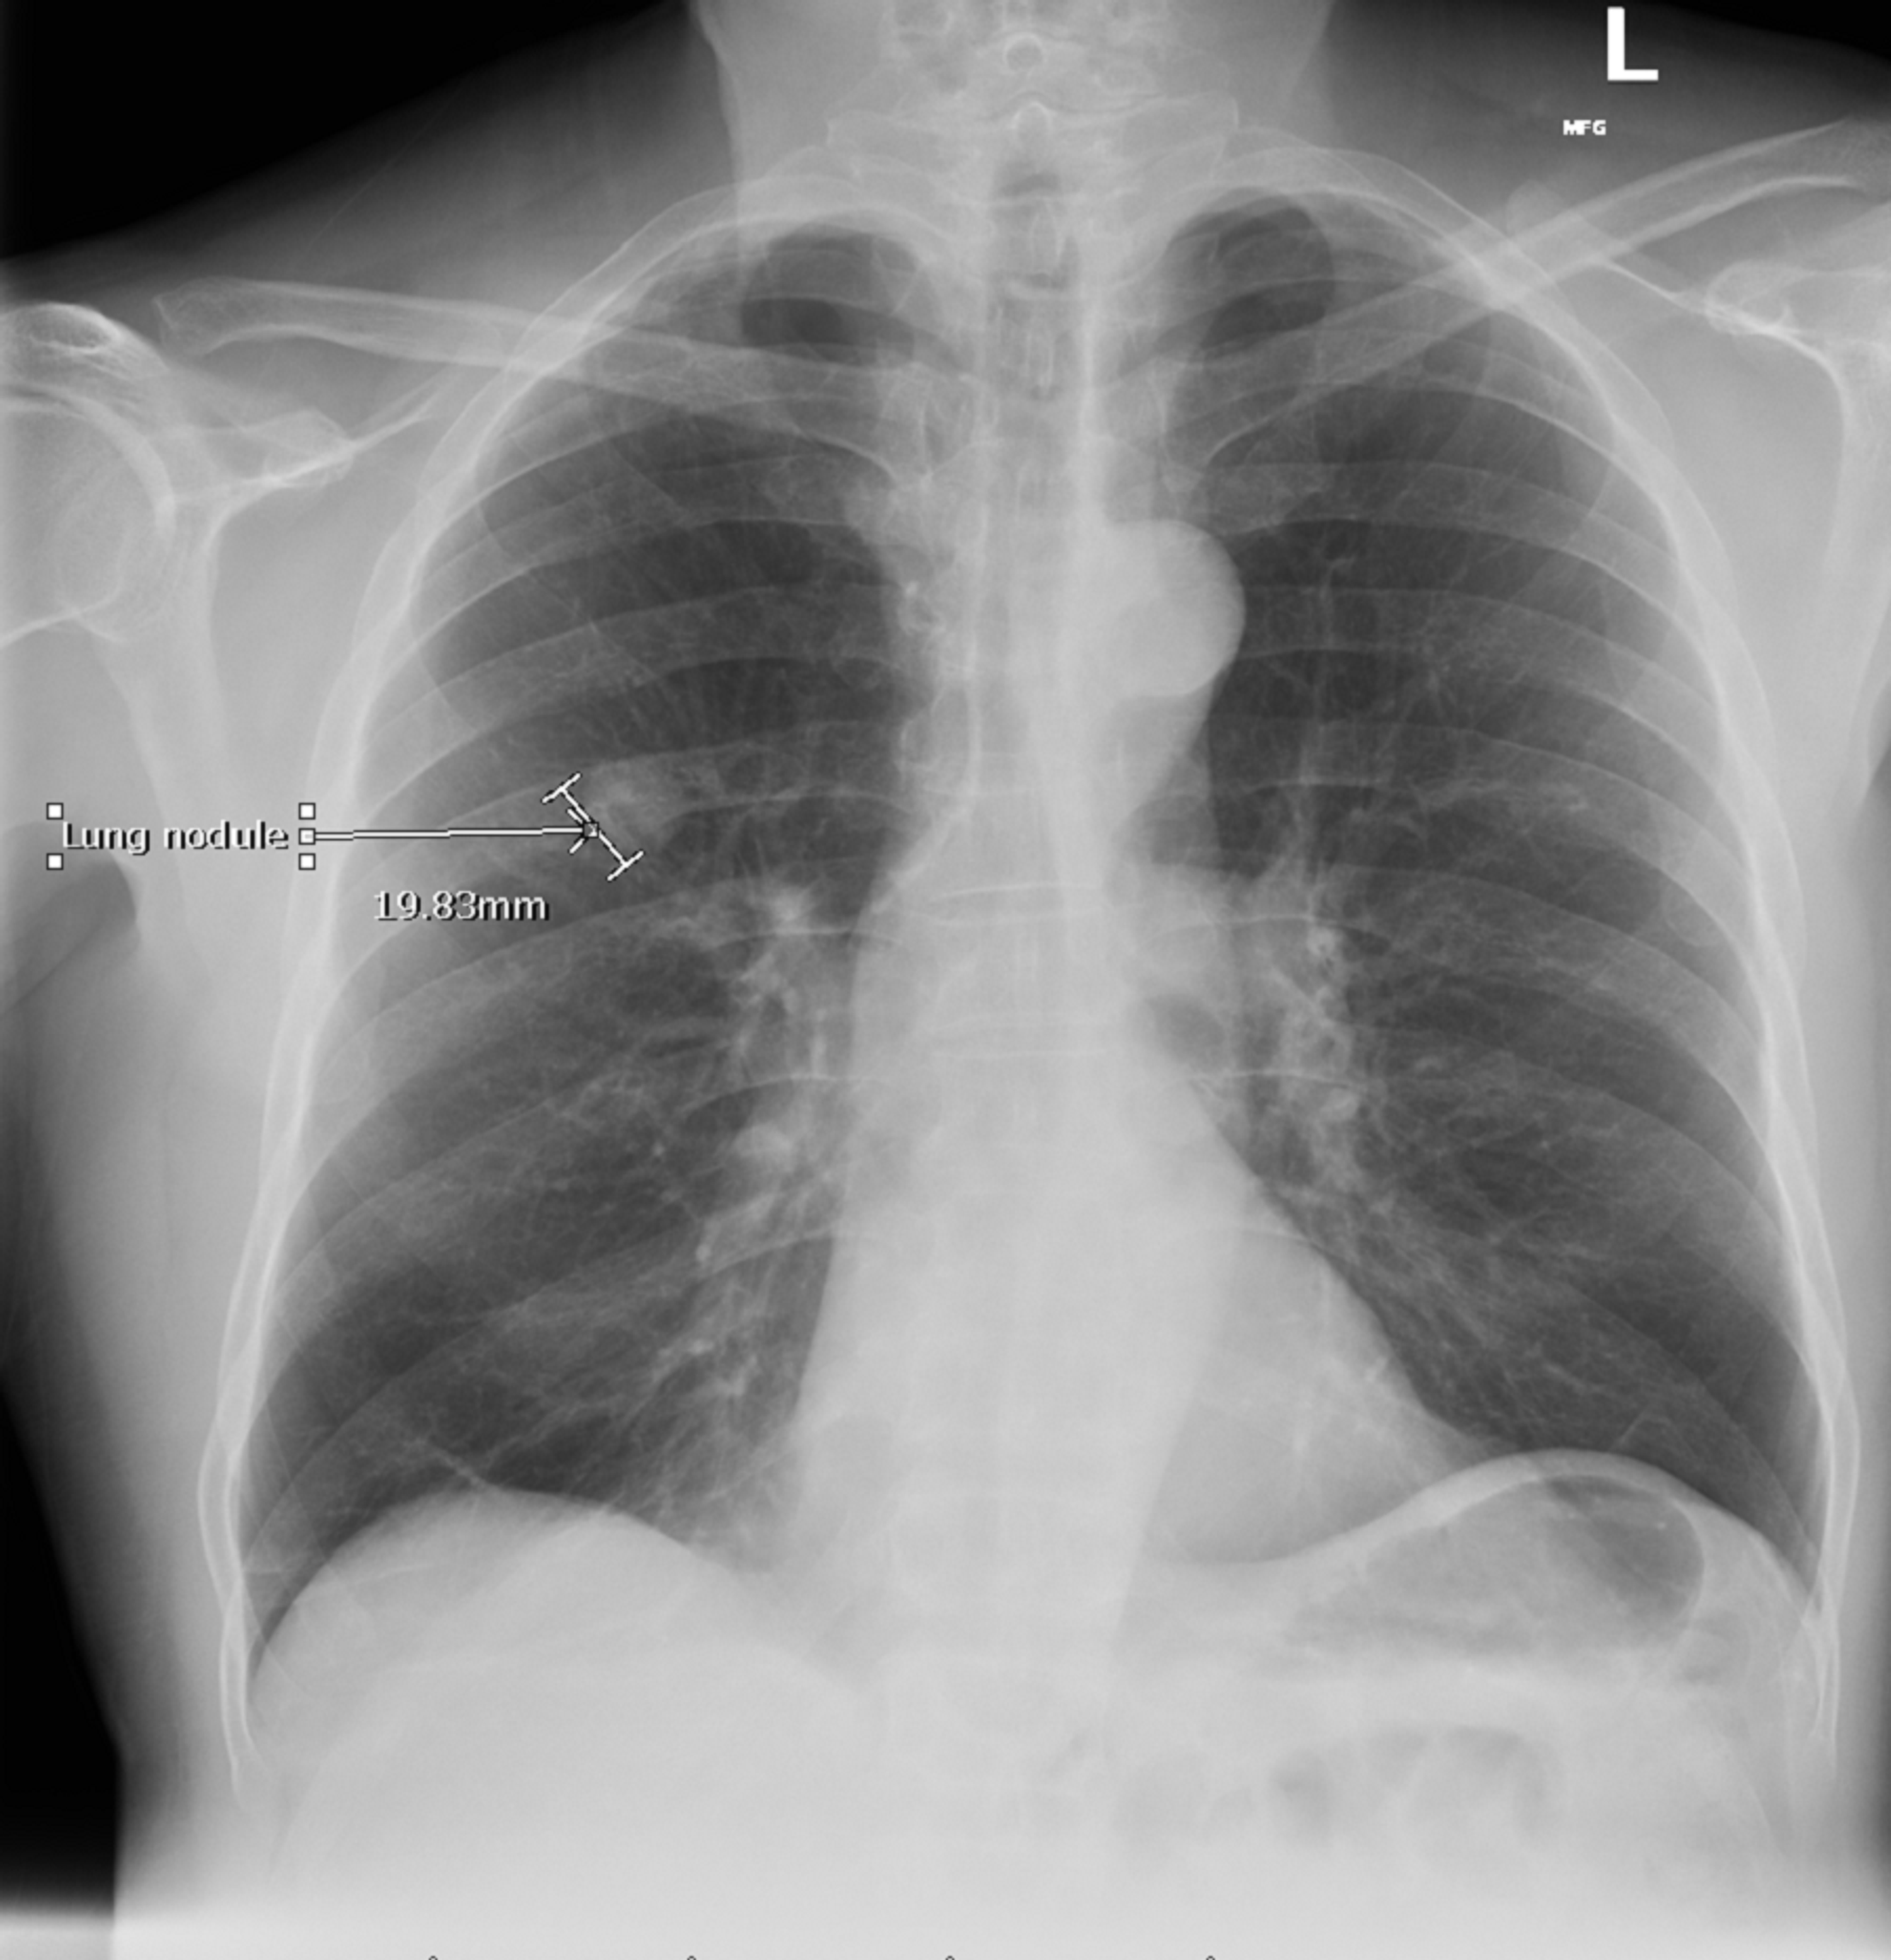

Chest Xray showing an apparent nodule in the left upper lung field

Chest Xray showing an apparent nodule in the left upper lung field Chest X Ray Nodule A lung nodule is a small mass of dense tissue on the lung. After that, you may need further testing to better characterize the nodule to help determine if it’s benign or. Less commonly, they can be caused by a more serious condition such as lung cancer. Are lung nodules a sign of lung. A lung nodule is an irregular. Chest X Ray Nodule.